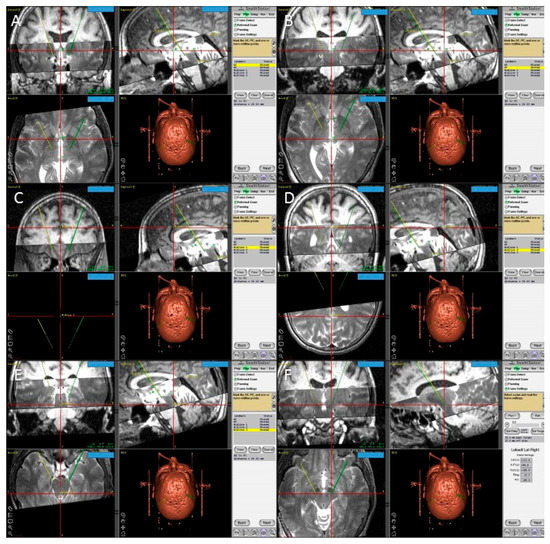

In the operation room, we used the FrameLink software, which is a part of StealthStation navigation system (Medtronic, Minneapolis, MN, USA) to confirm our calculations of the direct STN coordinates (Figure 5). This software compensates for head and frame tilt in any direction. The final coordinates for the procedure were derived from the two techniques, and subsequently adjusted using intraoperative electrical microrecording and macrostimulation.

Figure 5.

Screen shots from the Framelink software of the Stealthstation showing fused T1 and T2 MRI images of the patient and the planning process with identification of the posterior edge of the anterior commissure (AC) (A); the anterior edge of the posterior commissure (PC) (B); three midline points (C–E); and the final coordinates of the right subthalamic nucleus (F).